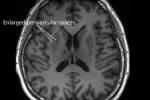

ورصد الباحثون انخفاضاً كبيراً في حجم المادة الرمادية لدى النساء في مرحلة ما بعد انقطاع الطمث.

وتركزت هذه الفروق، على وجه الخصوص، في الحُصين (الذي يؤدي دوراً رئيساً في التعلم والذاكرة)، والقشرة الشمية الداخلية (الضرورية لتكوين الذكريات والملاحة المكانية)، والقشرة الحزامية الأمامية (التي تساعد في الانتباه وتنظيم العواطف).

وقالت البروفيسورة باربرا سهاكيان، كبيرة مؤلفي الدراسة من قسم الطب النفسي: "إن مناطق الدماغ التي رصدنا فيها هذه الفروق هي نفسها مناطق تميل إلى التأثر بمرض ألزهايمر. وقد يجعل انقطاع الطمث هؤلاء النسوة أكثر عرضة لاحقاً للإصابة بالمرض. وعلى رغم أن ذلك لا يقدم التفسير الكامل، فإنه قد يساعد في تفسير سبب تسجيل ما يقارب ضعف حالات الخرف لدى النساء مقارنة بالرجال".